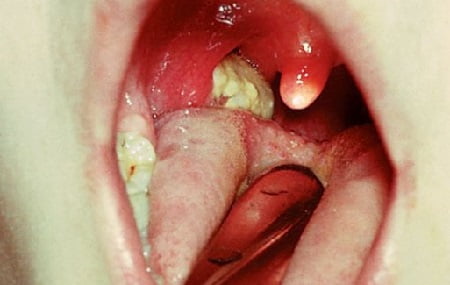

Дифтерия: фото

Как выглядят люди с диагнозом дифтерия, фото представлено ниже.

- толстые серые налеты, покрывающие горло и миндалины;

- Чаще всего (в 90% всех случаев заболеваемости) встречается дифтерия ротоглотки. Продолжительность инкубационного периода — от 2-х до 10 дней (от момента контакта человека с бактерионосителем). При проникновении палочки Леффлера на слизистую оболочки рта, она повреждает ее и вызывает некротизацию тканей. Этот процесс проявляется сильным отеком, образованием экссудата, который в дальнейшем заменяется фибриновыми пленками. Трудноотделяемый налет покрывает миндалины, может выходить за их пределы, распространяясь на соседние ткани.